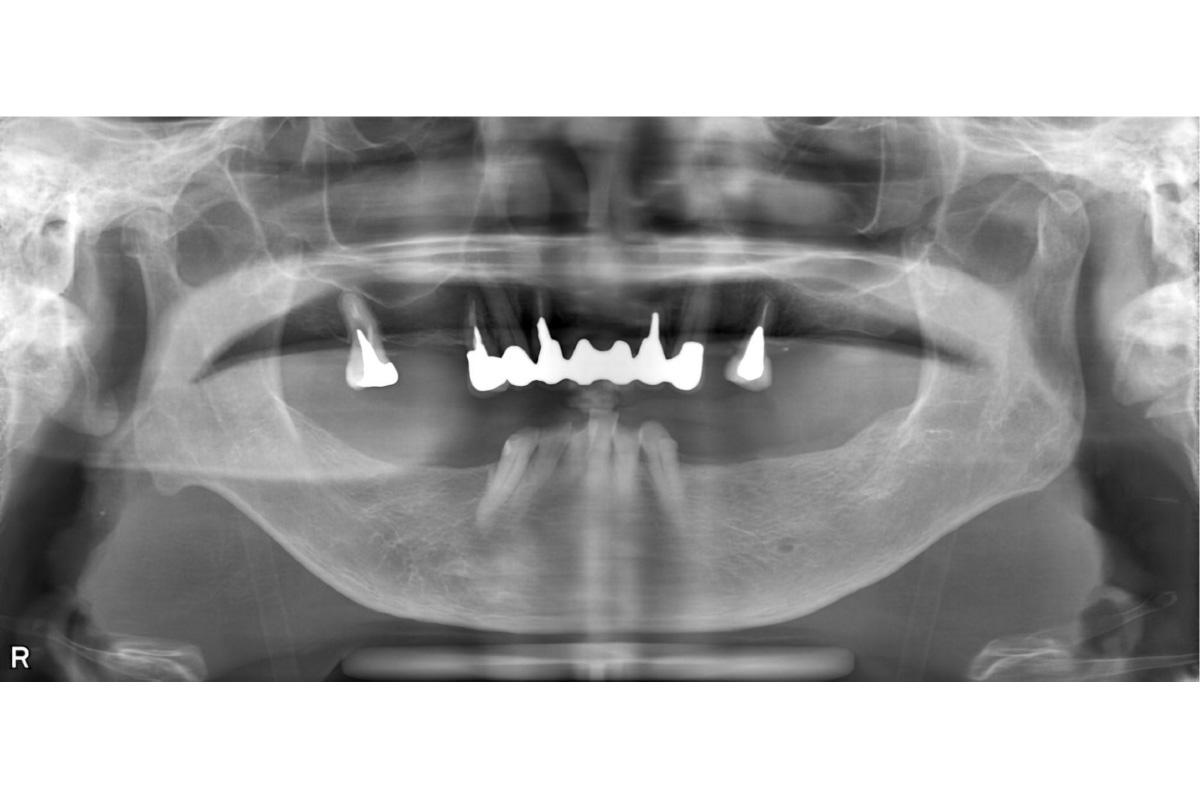

治療前